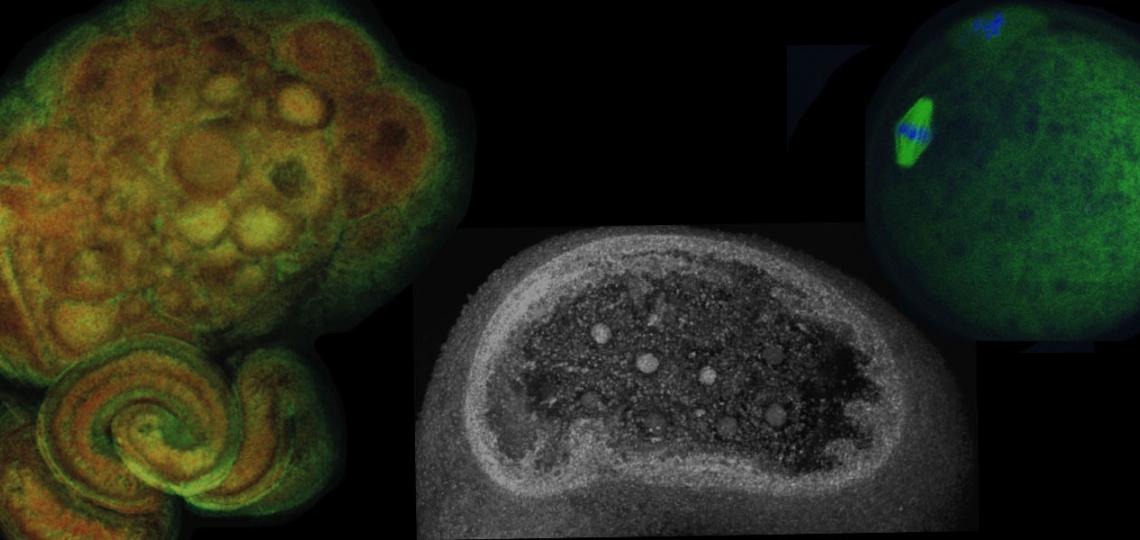

Our main research focus is in female reproductive biology and reproductive health. We primarily use novel genetic models to uncover genes necessary for female fertility and ovarian function. This includes developing models derived from ES cell targeting, CRISPR/Cas9 genetic engineering, and Cre-loxP recombination. Our research has uncovered a host of novel genes and pathways that control ovarian and uterine function, which when disrupted cause diseases such as primary ovarian insufficiency, infertility, and ovarian cancer.